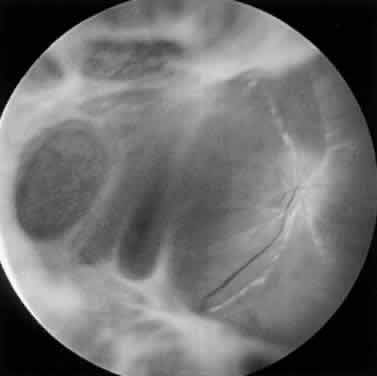

PORN syndrome is a progressive retinal infection with a distinct early, middle, and late stage (Table 2). The early stage is characterized by multifocal, homogeneous, opacified deep retinal lesions (Fig. 18). These lesions lack a granular border, which is a feature of CMV retinal infection. Lesions measure from 50 μm to several thousand microns in diameter and can be located peripheral to the arcades or in the macula at presentation. Early macular lesions are noted in up to 65% of patients, often appearing as central cherry-red spots67 (Fig. 19). Multifocal lesions rapidly progress to confluence and to full-thickness retinal involvement, forming large yellow-white areas of retinal necrosis with minimal retinal hemorrhage (Fig. 20). In eyes with initial peripheral involvement, progression often extends into the macula, and the entire retina may be involved within days. Primary retinal vascular inflammation does not appear to occur, although retinal vasculopathy in the form of sheathing and occlusion may be noted only within or adjacent to areas of retinal necrosis.67,68 A characteristic finding is perivenular lucency within areas of opaque retina, which may represent early clearing of necrotic retina71 (Fig. 21). Optic nerve abnormalities such as edema and hyperemia may occur and an afferent pupillary defect may be present secondary to severe asymmetric retinal necrosis or unilateral optic neuropathy. In end-stage PORN, dense white, plaque-like scarring with a “cracked-mud” appearance or retinal atrophy with peripheral hole formation may develop. Optic atrophy and narrowing of retinal vasculature typically are present.

Fig. 20. Equator-plus photograph in PORN syndrome reveals confluence of the retinal lesions and progression into the macula. Vitreous inflammation is absent.

Fig. 21. Perivenular lucency is noted as the retina adjacent to the retinal veins appears to be uninvolved by necrosis.